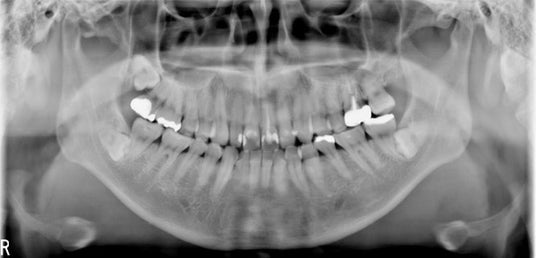

従来製品の概念を打ち破り、CdTe半導体センサーで撮影した膨大なボリュームデータから画像ノイズを除いて見たい部分だけ出力することができるので、【図3‐2】の画像のように頸椎の影響がなく、骨梁構造が明瞭に描出された鮮明な画像出力ができます。

【図3‐1】従来フラットパネルで撮影した画像

【図3‐2】CdTeセンサーで撮影した画像